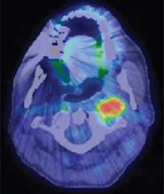

PET/CT image of patient with stage IVA HPV-positive squamous cell carcinoma of the head and neck